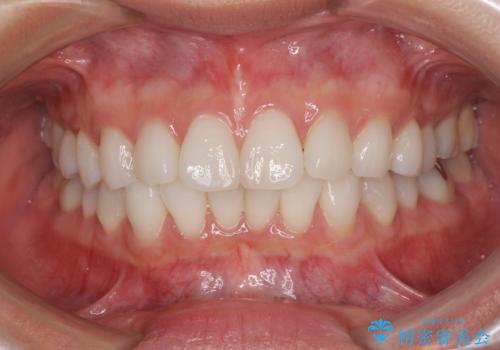

著しい八重歯が気になる インビザラインでの矯正治療